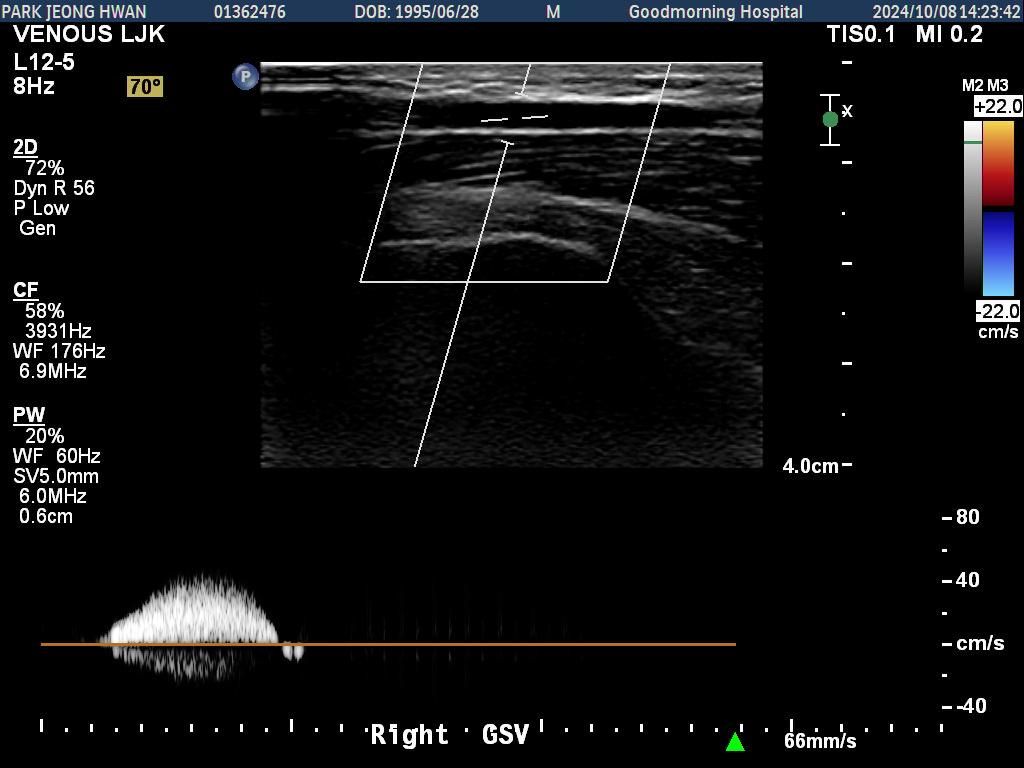

오른쪽 다리만 찍은 거구요. 종아리에서 사타구니까지 부분별로 찍었습니다.......................

• 1번 째 사진

• 2번 째 사진

• 3번 째 사진

• 4번 째 사진

• 5번 째 사진

• 6번 째 사진

• 7번 째 사진